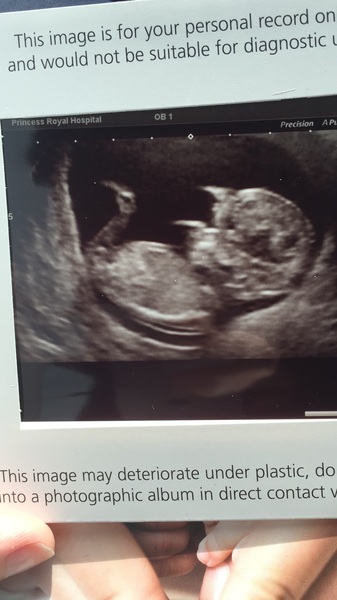

Popping back in as I had my first scan yesterday. Was so worried about it but baby was wriggling around happy as Larry and is set to be another big one...93rd centile for length.

NiceCupOfTeaAndASitDown · 04/08/2016 08:24

Here's my little bean Smile

Nice pic nicecup your baby has very long legs by the looks of things!

Congratulations Nicecup. That's a really lovely clear picture Smile

nicecup lovely pic, baby does look tall!

That's a good photo of your lo, nicecup!